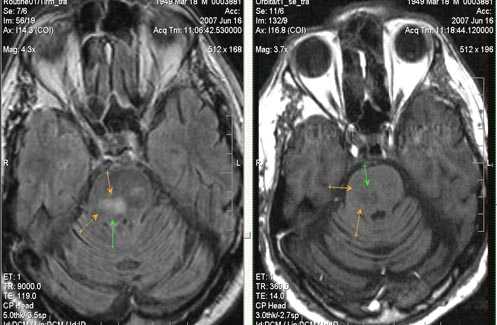

Внутримозговая гематома (граница острой и ранней подострой стадий - 3 суток), осложнившаяся внутрижелудочковым кровоизлиянием.

Внутримозговая гематома, поздний подострый период (14-21 день) с перифокальным отеком вокруг гематомы.

Внутримозговая гематома правой теменной доли. Граница поздней подострой и ранней хронической стадии. В Т2-ВИ виден ободок гемосидерина (стрелка).

Хочется подчеркнуть возможность МРТ в выявлении последствий геморрагического поражения - остается хорошо дифференцируемый по Т2 ободок гемосидерина, недоступный для визуализации при других методах нейровизуализации.

Стрелками показан ободок гемосидерина по периферии постишемической кисты.